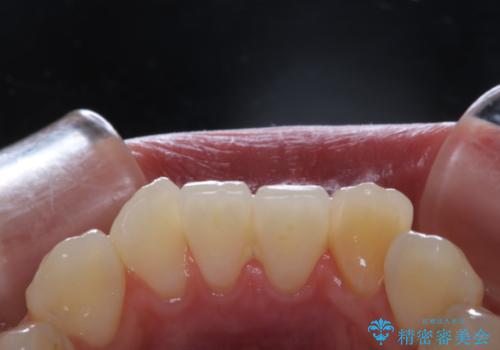

インビザラインでの矯正治療前にPMTCで歯のクリーニング

- 矯正治療の前にクリーニング希望で来院されました。PMTC30分コースを行いました。

PMTCは、国家資格取得者の歯科衛生士により、専門的な機械や材料を使用してのクリーニングです。一人一人の患者様のお口の状態に合わせたクリーニングを行います。

矯正治療は、歯を動かすため歯肉にも負担がかかります。そのため、矯正前にしっかりクリーニングを行い健康なお口の状態にしておくことが大切です。